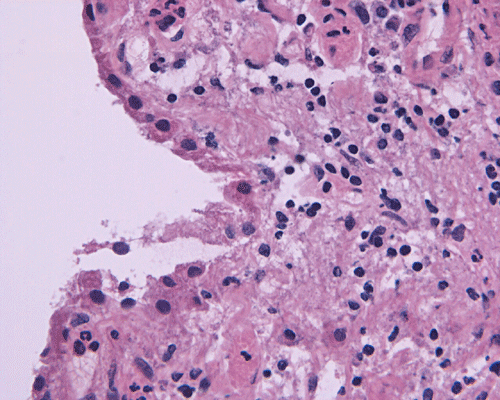

Intraoperative consultation: The specimen is that of a streotactic biopsy and is very small. The intraoperative cytologic preparation was rather hypocellular. Small clusters of cells with bland nuclei and foamy cytoplasm are present and they are highly suggestive of foamy histiocytes (Panel C). On frozen section, there are many small lymphocytes in a "pink" background that can be a granulomatous process (Panel D). In some areas, many foamy macrophages are present and one particular fragment appear to be a possible portion of a wall of structure with lining cells suggestive of macrophages (Panel E).

Paraffin sections: The entire volume of the tissue is made up of a granulomatous inflammation with poorly formed granuloma (Panel F, G, and H). The density of the lymphocytes is variable in different areas. In some areas, there is a rather intense lymphocytic infiltration accompanied by scant atypical cells with enlarged nulcei and prominent nucleoli (arrows in Panel I and J, Panel J is a higher magnification of Panel I). These atypical cells are quite easy to be missed. No microorganisms were identified by acid fast stain, PAS stain or GMS stain. The lymphocytes but not the atypical cells are positive for CD20 (Panel K) or CD3 (Panel L). The granulomatous background is strongly positive for CD68 (Panel M). Only rather faint positive staining for placental alkaline phosphatase (PLAP) is demonstrated and the interpretation is difficult as they are present in areas with crush artifact (Panel N). Many of the large, atypical cells are positive for CD117 (c-kit) (Panel O).

Granulomatous changes are common findings in germinomas and intracranial germinomas follow this general trend 3, 4, 5. It can be extensive. This feature is particularly problematic in neuropathologic when stereotactic biopsy is performed and the amount of tissue available for examination is limited as illustrated in this case. During intraoperative consultations, a frozen section diagnosis of granulomatous inflammation should prompt additional sampling as isolated granulomatous inflammation of infectious origin and sarcodosis are quite uncommon in the pineal gland.